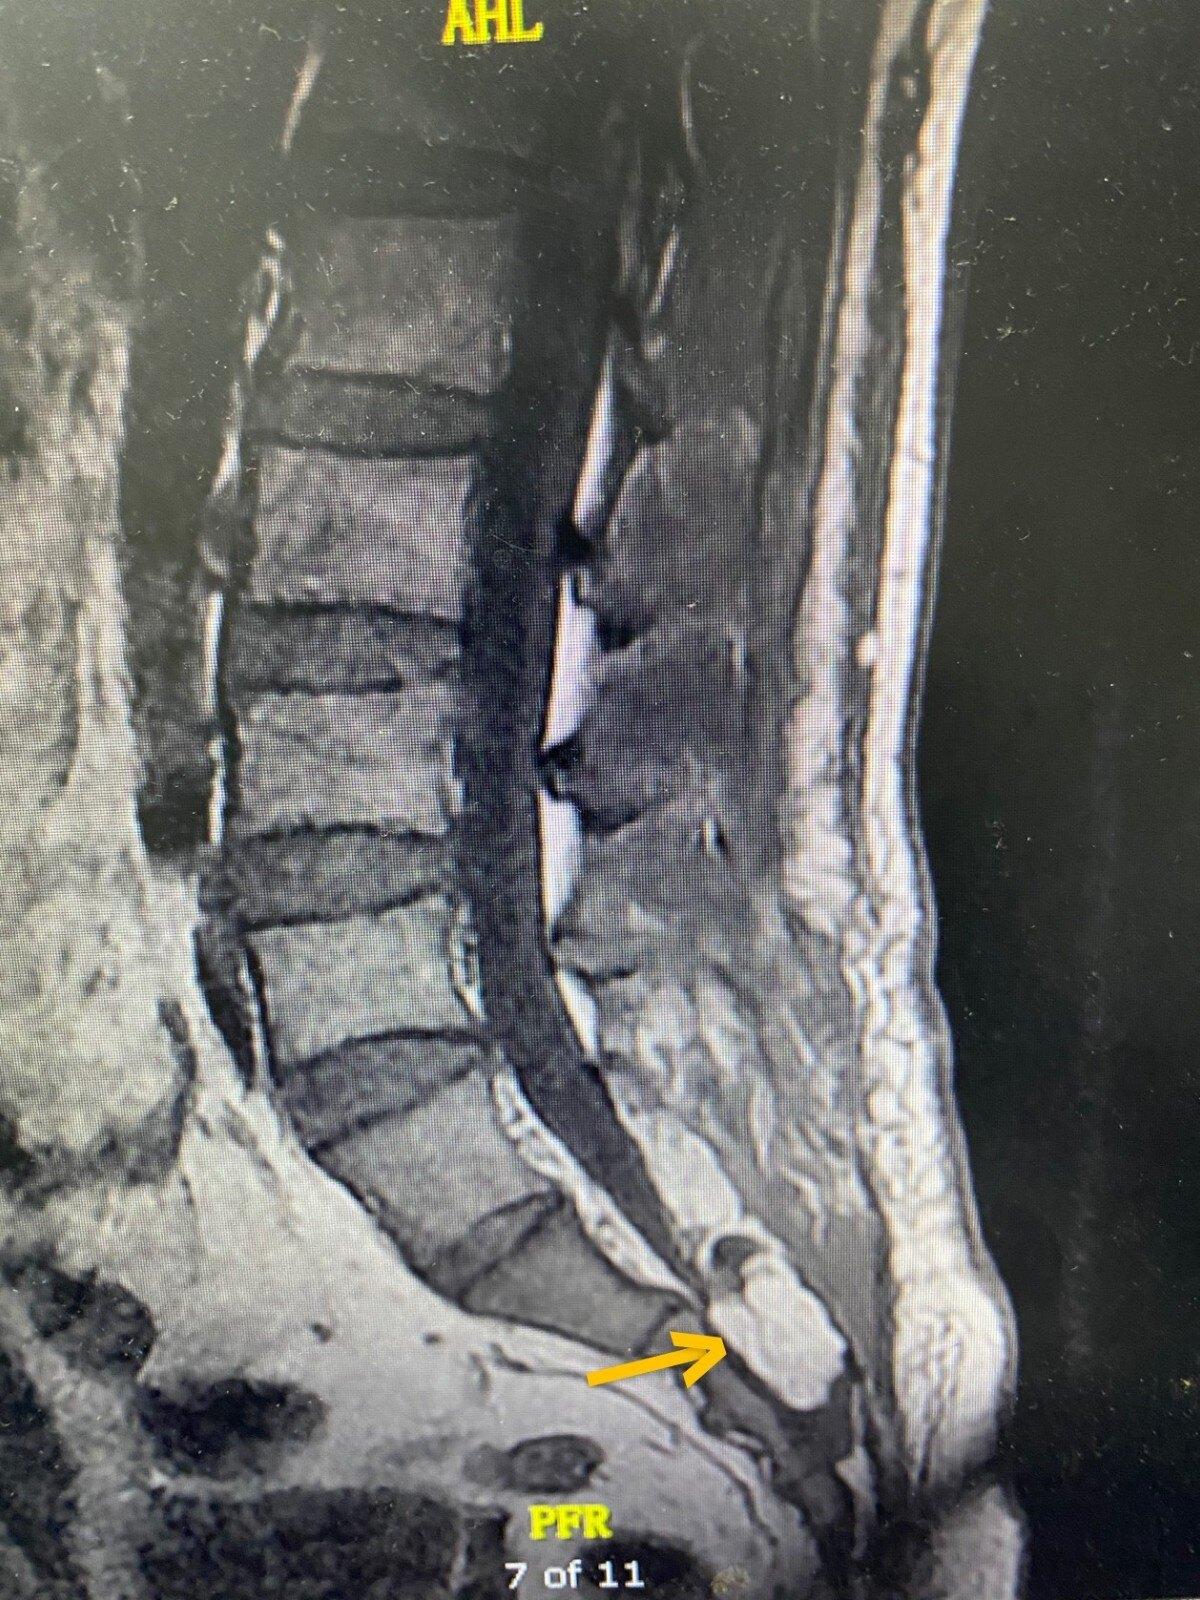

骶骨囊肿图片

骶尾部囊肿